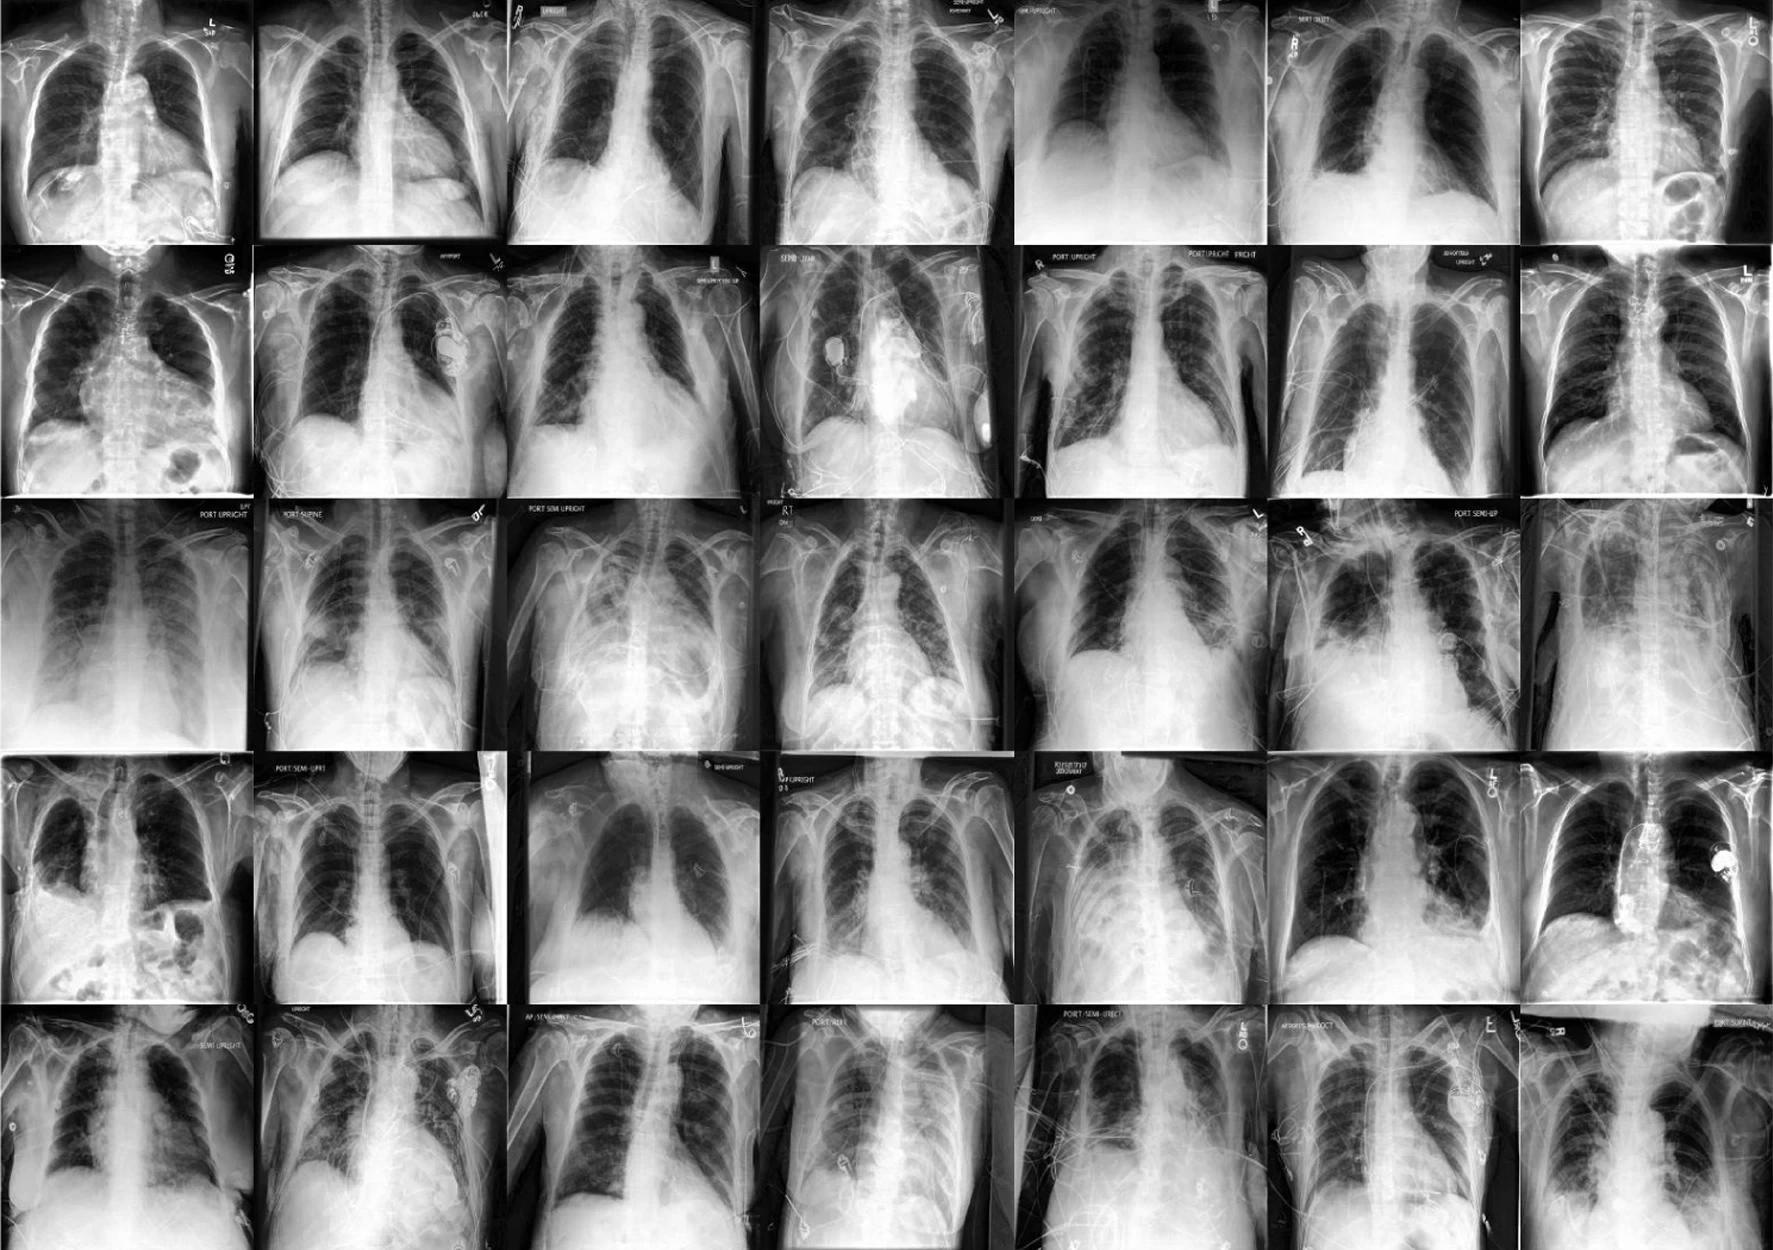

Researchers used two big public radiology datasets, CheXpert and ChestX-ray, to create generative and diagnostic models for chest X-rays. After training on 201,055 chest X-ray instances, dermatologists evaluated the model's ability to capture primary characteristics on 488 synthetic pictures from regular and high-risk classes. They assessed the picture quality to offer a diagnosis for up to three of the approximately 20,000 common illnesses.